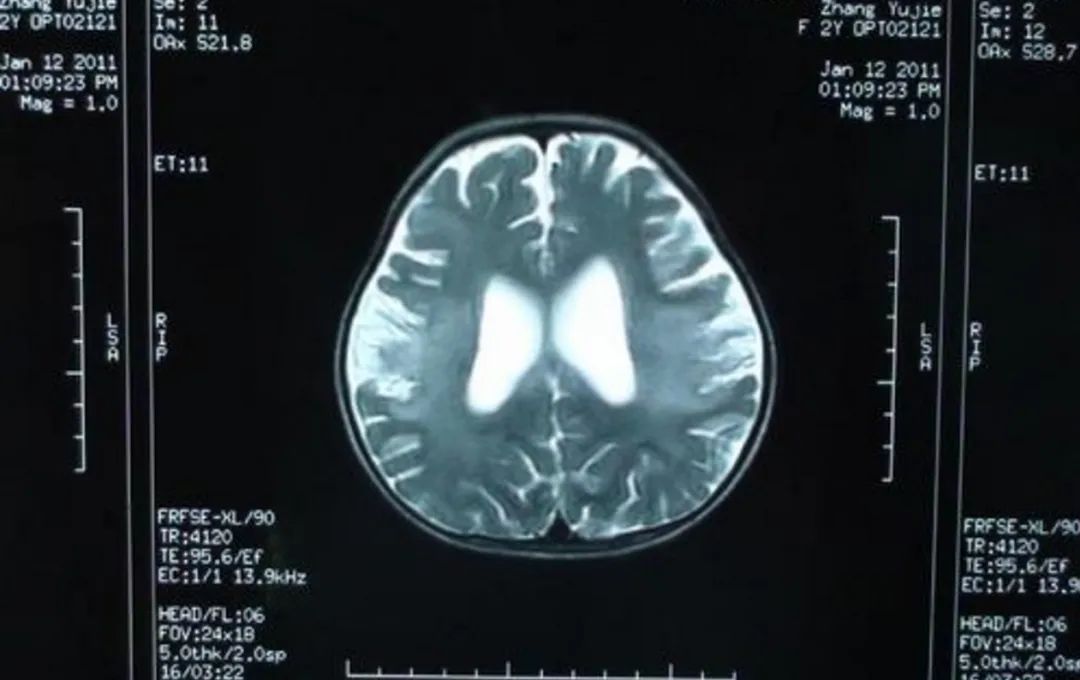

遗憾的是,妻子至今仍然没有醒来。最近,妻子需要再进行一次清除脑部积水的手术,医院下达了《催缴通知书》。

图片仅为示意,与本文无关